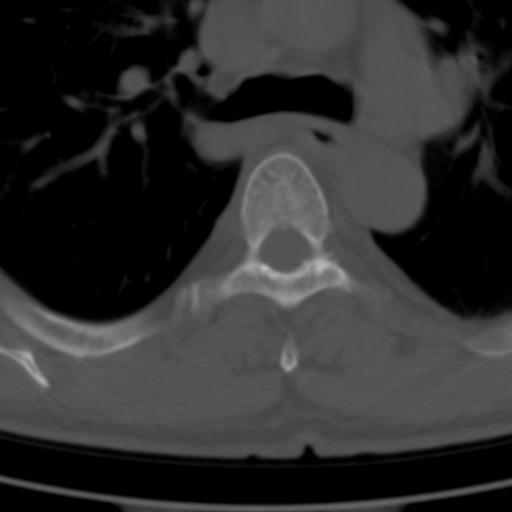

标题: CT25189:胸椎ct,请会诊!

既往食管癌,现行ct检查!

中上段食道癌,椎体轻度退变。

支持中上段食道癌,椎体轻度退变,必要时做ect。